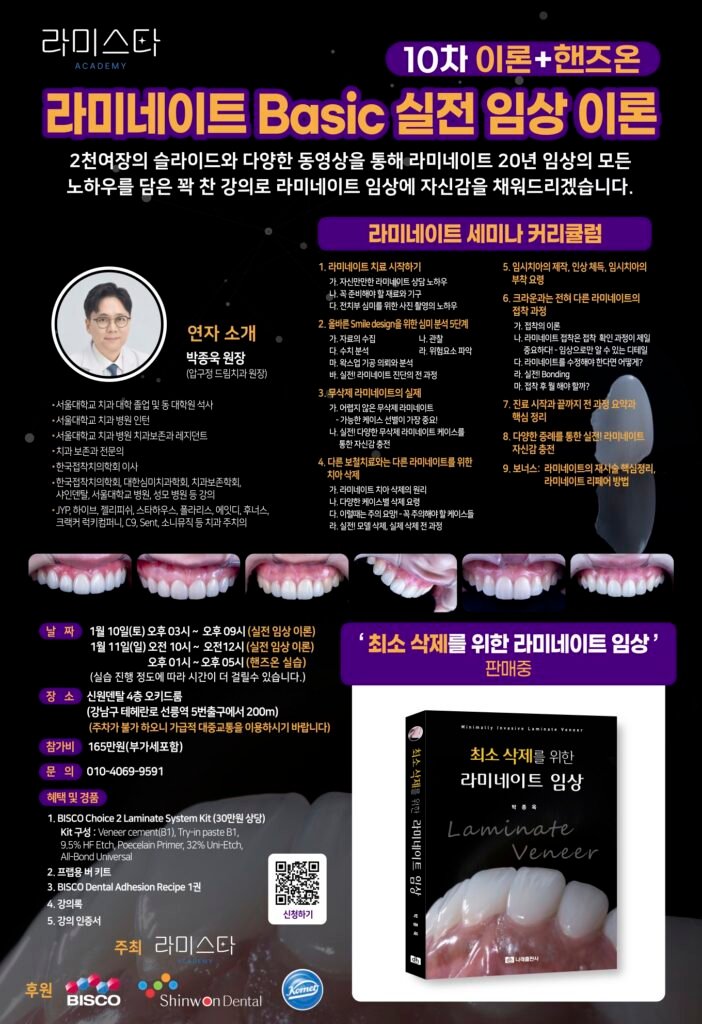

사진 2~4 — 왁스업 정밀진단 과정

라미네이트의 핵심은 ‘삭제량 예측’입니다.

디지털 왁스업으로 치료 후 형태와 삭제량을 미리 시뮬레이션함으로써

치아를 불필요하게 손상시키지 않도록 설계했습니다.